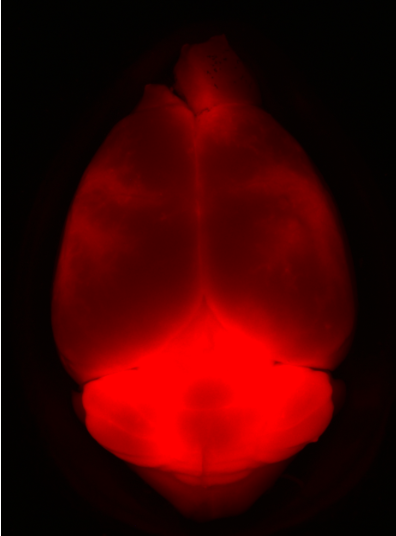

Her research focuses on the glymphatic system, a brain-wide network of perivascular pathways and aquaporin-4 (AQP4) water channels, that facilitates the exchange of fluid throughout the brain and is important for the transportation and clearance of solutes and brain waste. Glymphatic system dysfunction occurs in normal aging as well as many neurological disorders, such as Alzheimer's disease, Parkinson’s disease, stroke, traumatic brain injury, and cerebral small vessel disease.

Current projects in the lab are examining neutrophil extracellular trap-induced glymphatic dysfunction in Alzheimer’s disease and menopause-induced glymphatic dysfunction as a possible risk-factor for Alzheimer’s disease. The Braun lab is also examining differences in localization of AQP4 water channels across mammalian species with varying levels of cortical folding and how this may impact glymphatic function.

Dr. Braun’s PhD work examined how neutrophil extracellular traps (NETs) decreased cerebral blood flow (CBF), increased edema, and worsened behavioral outcomes following TBI (Sci Adv 2020). In addition, she led projects that examined how macrophages activate pro-inflammatory T helper cells following TBI via a TLR4-dependent mechanism (J Immunol 2017) and how cannabinoid receptor-2 activation reduces neuroinflammation after TBI by shifting macrophages to more anti-inflammatory phenotypes (Brain Behav Immun 2018). Her work also examined how remote ischemic conditioning following intracerebral hemorrhage promotes hematoma resolution via AMPK-dependent immune regulation of macrophages (J Exp Med 2018). During her postdoctoral work she examined how changes in AQP4 mediate glymphatic impairment following blast TBI using both human post-mortem brain tissue, human MRI data, and a mouse model of mild repetitive blast injury (Brain 2024).